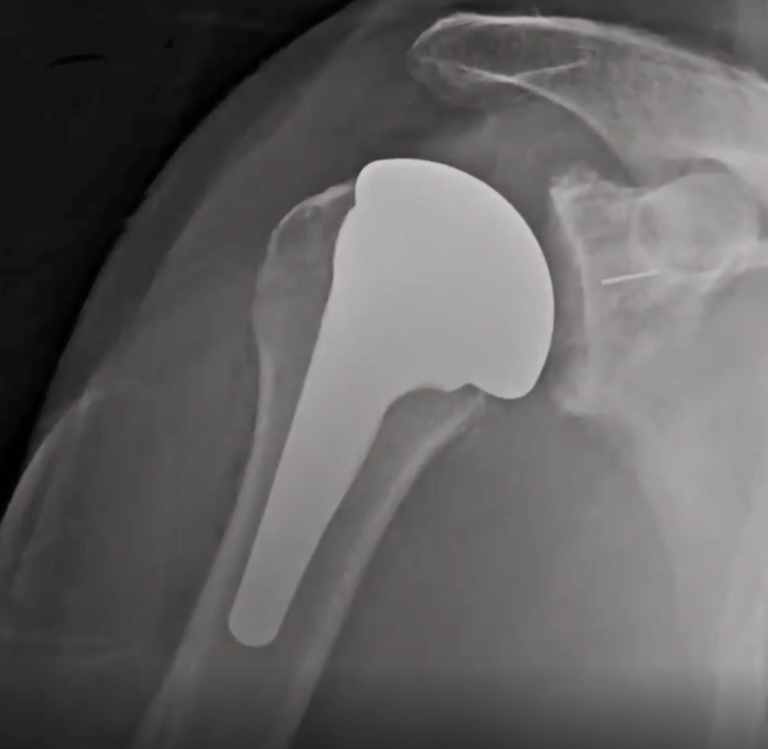

La coiffe des rotateurs étant détériorés, l'action du muscle deltoïde est privilégier pour animer l'épaule. Pour ce faire: les surface articulaire sont inversées:

une sphère est placée sur l'omoplate ( 4)

une cupule est placée au sommet de l'humérus ( 5).

L'intervention nécessite une à deux nuit d'hospitalisation.

La kinésithérapie débute le jour ou le lendemain de l'intervention

Une immobilisation légère de 4 semaines est à respecter hors des séances de kinésithérapie.